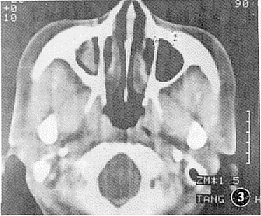

8例均行副鼻窦轴位平扫,层厚5 mm,层距5 mm。8例均显示受累副鼻窦粘膜肥厚,密度不均匀6例,均匀者2例;2例显示骨质虫蚀样破坏,1例骨质变薄,窦腔扩大,3例见软组织块影,CT值50~60 HU(图3);4例可见斑片状或条状高密度钙化影,CT值124~286 HU(图4);但未见侵及眶内或颅内扫描征象。

图3 CT所见窦腔内软组织肿块影